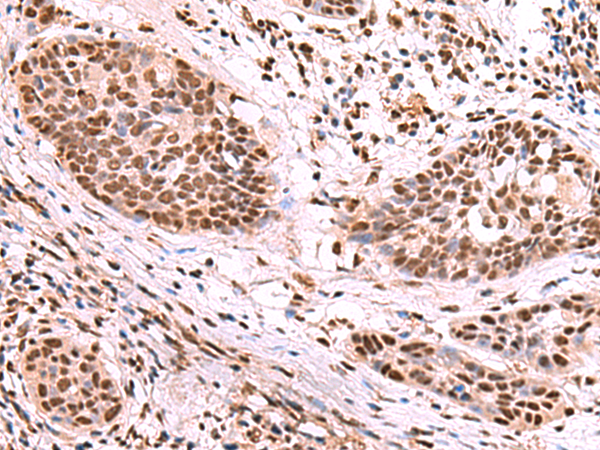

分类: 科研抗体货号: P10166别名: dJ283E3.1应用: IHC反应种属: Human, Mouse